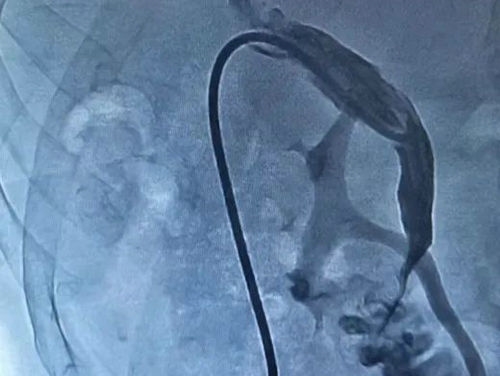

决定行“肝动脉造影”

术中发现肝右动脉远端一细小分支出血

▲ 箭头处为肝动脉出血征象

▲ 栓塞后肝动脉出血停止